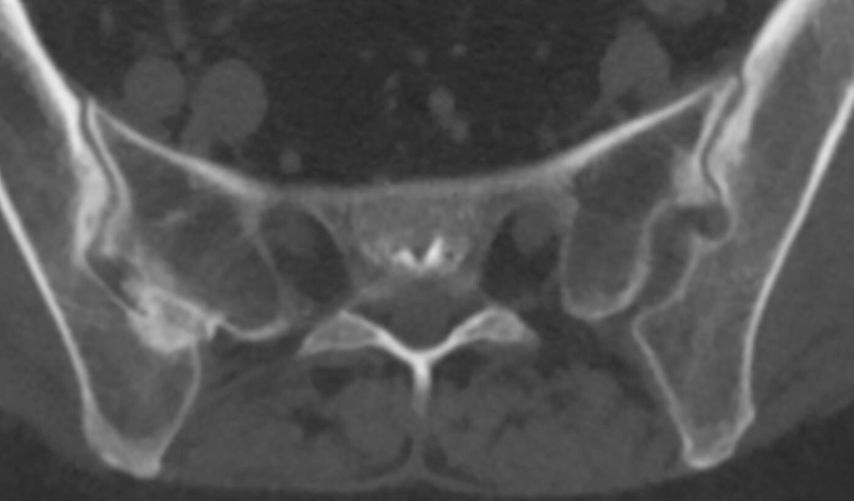

Abb. 2: Computertomografie: überlagerungsfreie CT-Darstellung der knöchernen Veränderungen an den Sakroiliakalgelenken mit Sklerosierungen, Erosionen und Ankylosen

Auch die CT hat als röntgenstrahlenbasiertes Verfahren ihre Stärke im Bereich der knöchernen Strukturen, mit dem Vorteil einer überlagerungsfreien Darstellung (Abb. 2). Die Auflösung ist für die meisten Fragestellungen ausreichend, erreicht jedoch nicht das Niveau von Röntgen-Detailaufnahmen oder hochauflösenden Ultraschalluntersuchungen. Die CT ist prinzipiell auch für großräumige Untersuchungen geeignet, wobei die erhebliche Strahlenbelastung als limitierender Faktor zu bedenken ist. Die Verfügbarkeit ist allgemein gut, und die Untersuchungsdauer ist kurz. Allerdings ist eine CT mit einem gewissen geräte- und untersuchungstechnischen Aufwand verbunden und dementsprechend teuer.